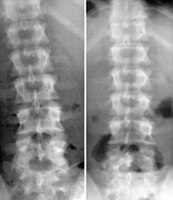

In recent years, specialized NUCCA Upper Cervical Doctors have developed a way to safely align just this "Atlas" bone, clearing the central pathway that your body uses for nerve communication and balancing the entire entire spine.

Misaligned Skull on Atlas and Neck Aligned Neck, Atlas and Skull

Reprinted with permission from Daniel O. Clark, D.C.

uppercervicalillustrations.com

This complex, little known type of health care that involves only the correction of the"Atlas" in the neck, can restore proper function of the brain stem and nerves of your entire body. And that means healing.